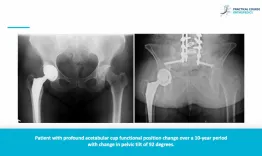

In this Literature Review, Panuwat Silawatshananai (Bangkok International Hospital) discusses a compelling study published in The Journal of Arthroplasty

Excellence in hip research award: Pelvic tilt and cup position change significantly in most young patients 10 years after hip arthroplasty

Panuwat Silawatshananai